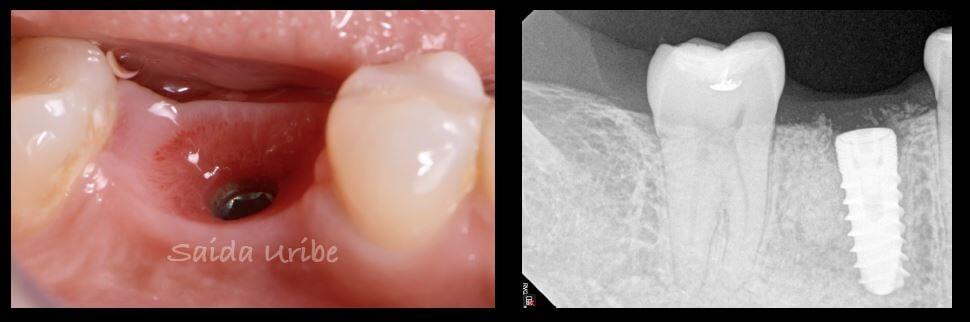

Un implante dental es una estructura cilíndrica parecida a un tornillo que se coloca quirúrgicamente en el hueso maxilar para sustituir la raíz de un diente. Una vez que el implante se integra al hueso, se fabrica una prótesis a medida que se coloca sobre este.